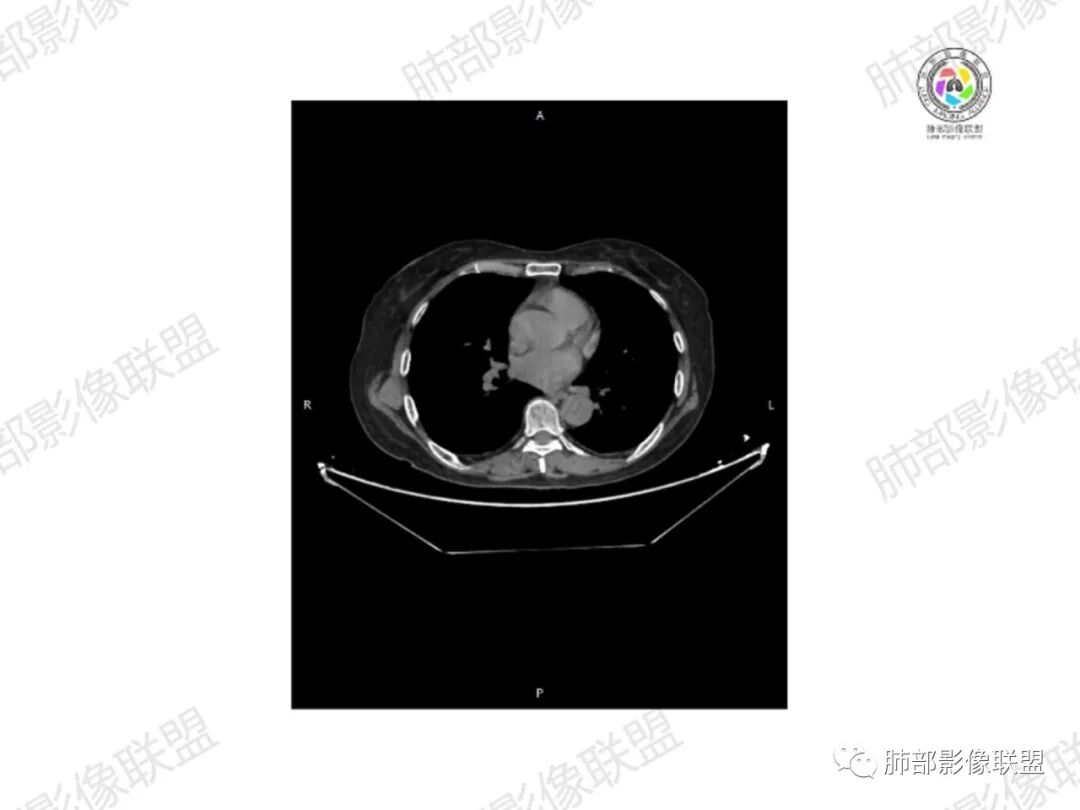

1.老年女性,直肠癌术后放疗后5年,右臀部疼痛4个月,加重半月

2.右髂骨轻度变形伴广泛骨质吸收破坏,边界不清且突破骨皮质。近中线区以溶骨性破坏为主,髂骨翼一侧则成骨性改变明显,骨表面见垂直骨针或花边样高密度瘤骨。

3.患骨多处皮质断裂,符合病理性骨折。注意折端可能会形成骨痂,但本例无论是形态还是部位都不符合骨痂。

4.患骨两旁(即盆骨内外)见边界不清的较大范围软组织快影,其间偶见骨化影。

5.双肺多发类圆形结节影,边界清楚,随机分布,其间多见钙化密度影。

6.双肺门及纵隔未见肿大淋巴结。

1.边界不清的骨质吸收破坏,溶骨明显,骨皮质突破,软组织肿块,种种迹象表明其恶性无疑!

2.但注意这是有“成骨”的恶性骨肿瘤!我们知道老年患者的骨原发性恶性肿瘤“成骨”非常少见。少数转移瘤可为成骨型或混合型,女性患者如乳腺癌骨转移等。在男性,最典型的成骨转移是前列腺癌。

本例右侧髂骨具有较为典型的“骨肉瘤”影像学特征,有边界不清的吸收破坏、有新生骨、形成软组织肿块等等。